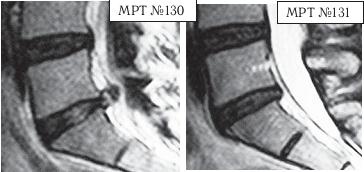

На МРТ № 130 наблюдается состояние поясничного отдела позвоночника после двух хирургических операций: рецидив грыжи межпозвонкового диска в сегменте LV-SI.

На МРТ № 131 наблюдается состояние поясничного отдела позвоночника после лечения методом вертеброревитологии.

Рецидив грыжи межпозвонкового диска после двух хирургических операций — и это у молодого человека в возрасте 16 лет! Чрезмерное увлечение компьютером, малоподвижный образ жизни основательно подорвали его здоровье. Всё это привело к тому, что в течение года, начиная с пятнадцатилетнего возраста, он практически не выходил из больниц. После первой хирургической операции на позвоночнике, менее чем через месяц, боли возобновились. Спустя два месяца его вновь прооперировали по поводу рецидива — грыжи межпозвонкового диска. После второй хирургической операции боли наблюдались практически два месяца подряд, потом затихли, но полностью так и не прошли. Через пять месяцев появилась слабость в обеих ногах. Сделали снимки МРТ, диагностировали рецидив грыжи межпозвонкового диска, естественно рекомендовали сделать очередную третью хирургическую операцию. В промежутках между операциями молодой пациент несколько раз находился на стационарном лечении в неврологическом отделении городской больницы. Именно там, после того как у парня была диагностирована очередная грыжа, лечащий врач посоветовал не спешить с третьей операцией и порекомендовал ему обратиться ко мне в клинику. Конечно, этот случай был далеко не простым и пришлось основательно потрудиться как мне, так и самому пациенту над восстановлением его здоровья. Но зато результат порадовал всех тех, кто непосредственно участвовал в этом процессе, и кто косвенно ему способствовал. Можно сказать, ещё одна судьба была изменена и молодой человек спасён от инвалидной коляски.